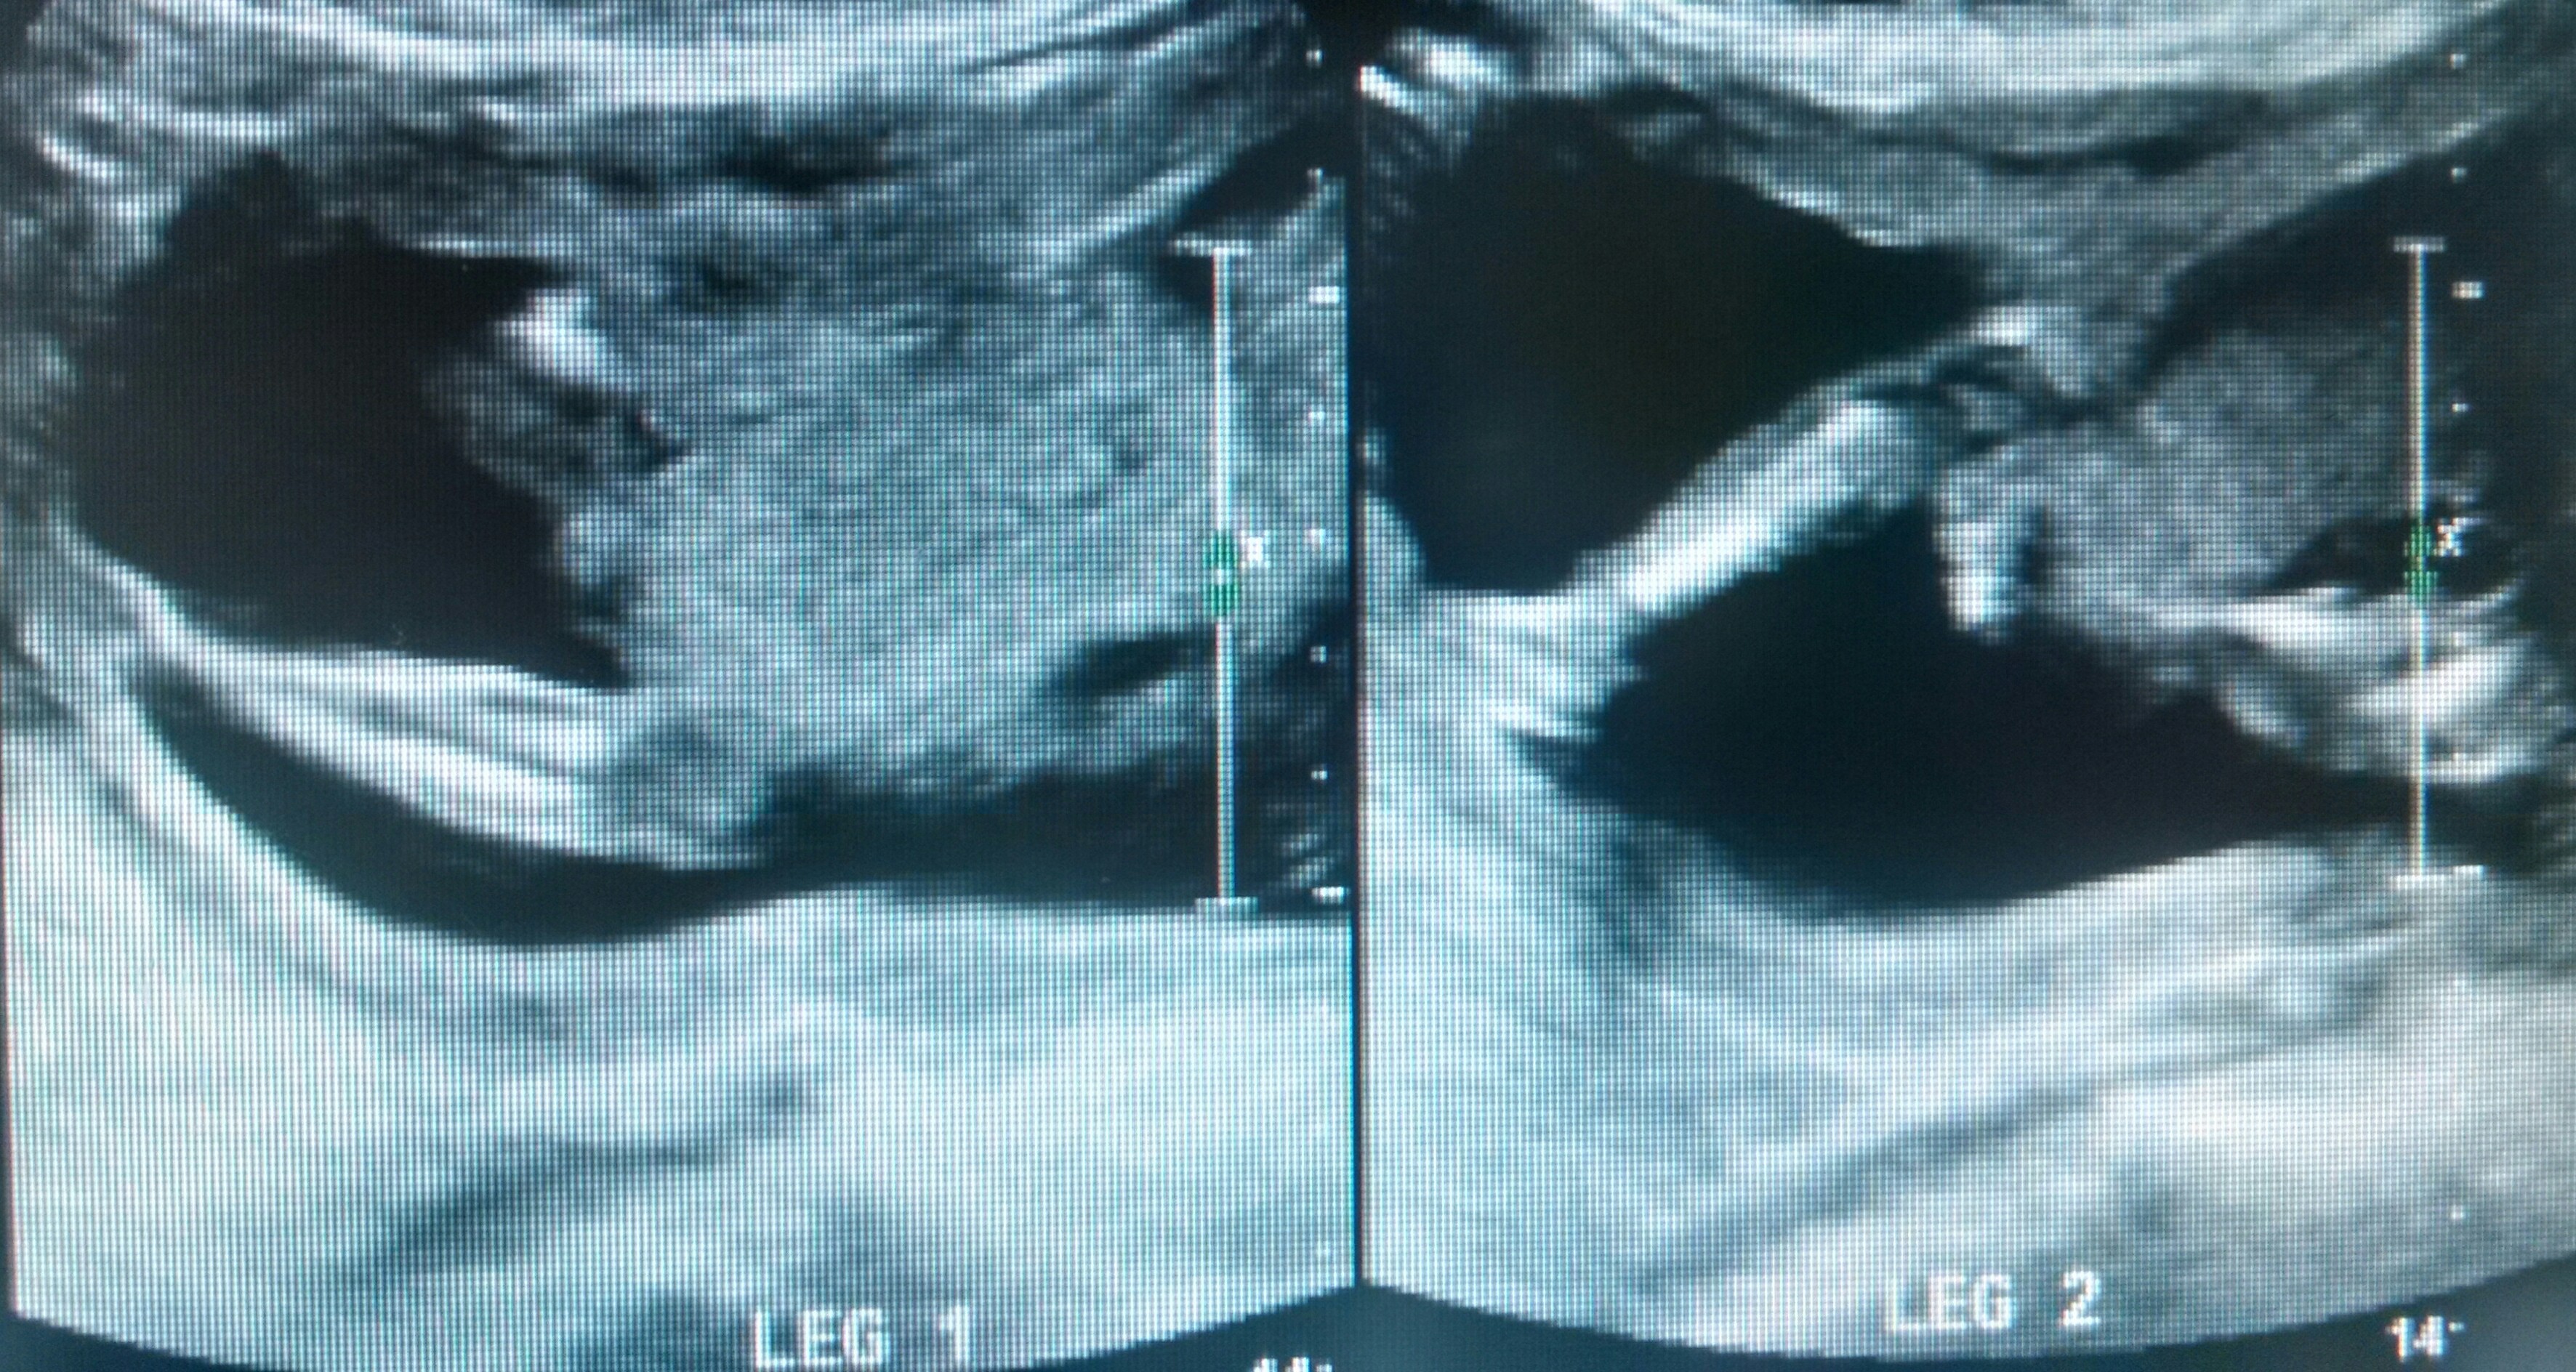

Tech wasn't 100% sure cause baby was on stomach and legs close together, I have 4 girls and was hoping this could by chance be a boy!! I was 19 weeks and 4 days! Thank you!!